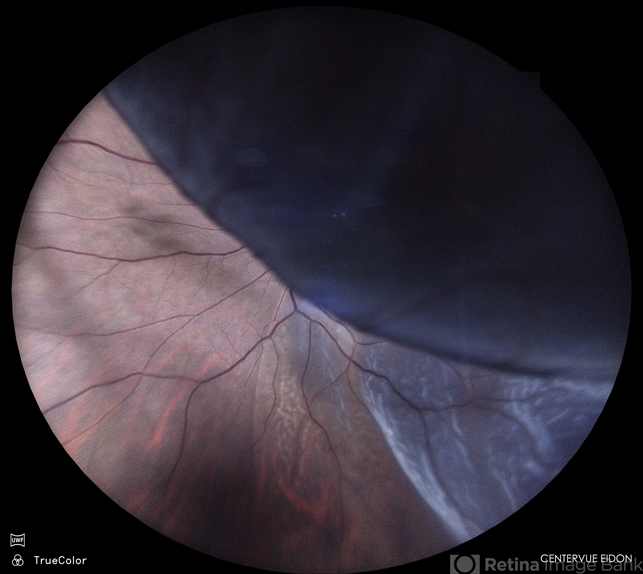

- Color fundus photograph of a 50 year old male with retinal detachment.